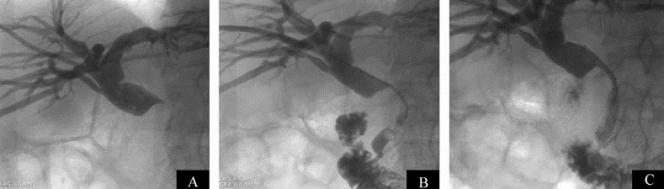

图21-37 肝脓肿经皮抽吸引流

A.治疗前CT;B.治疗后复查脓腔基本消失